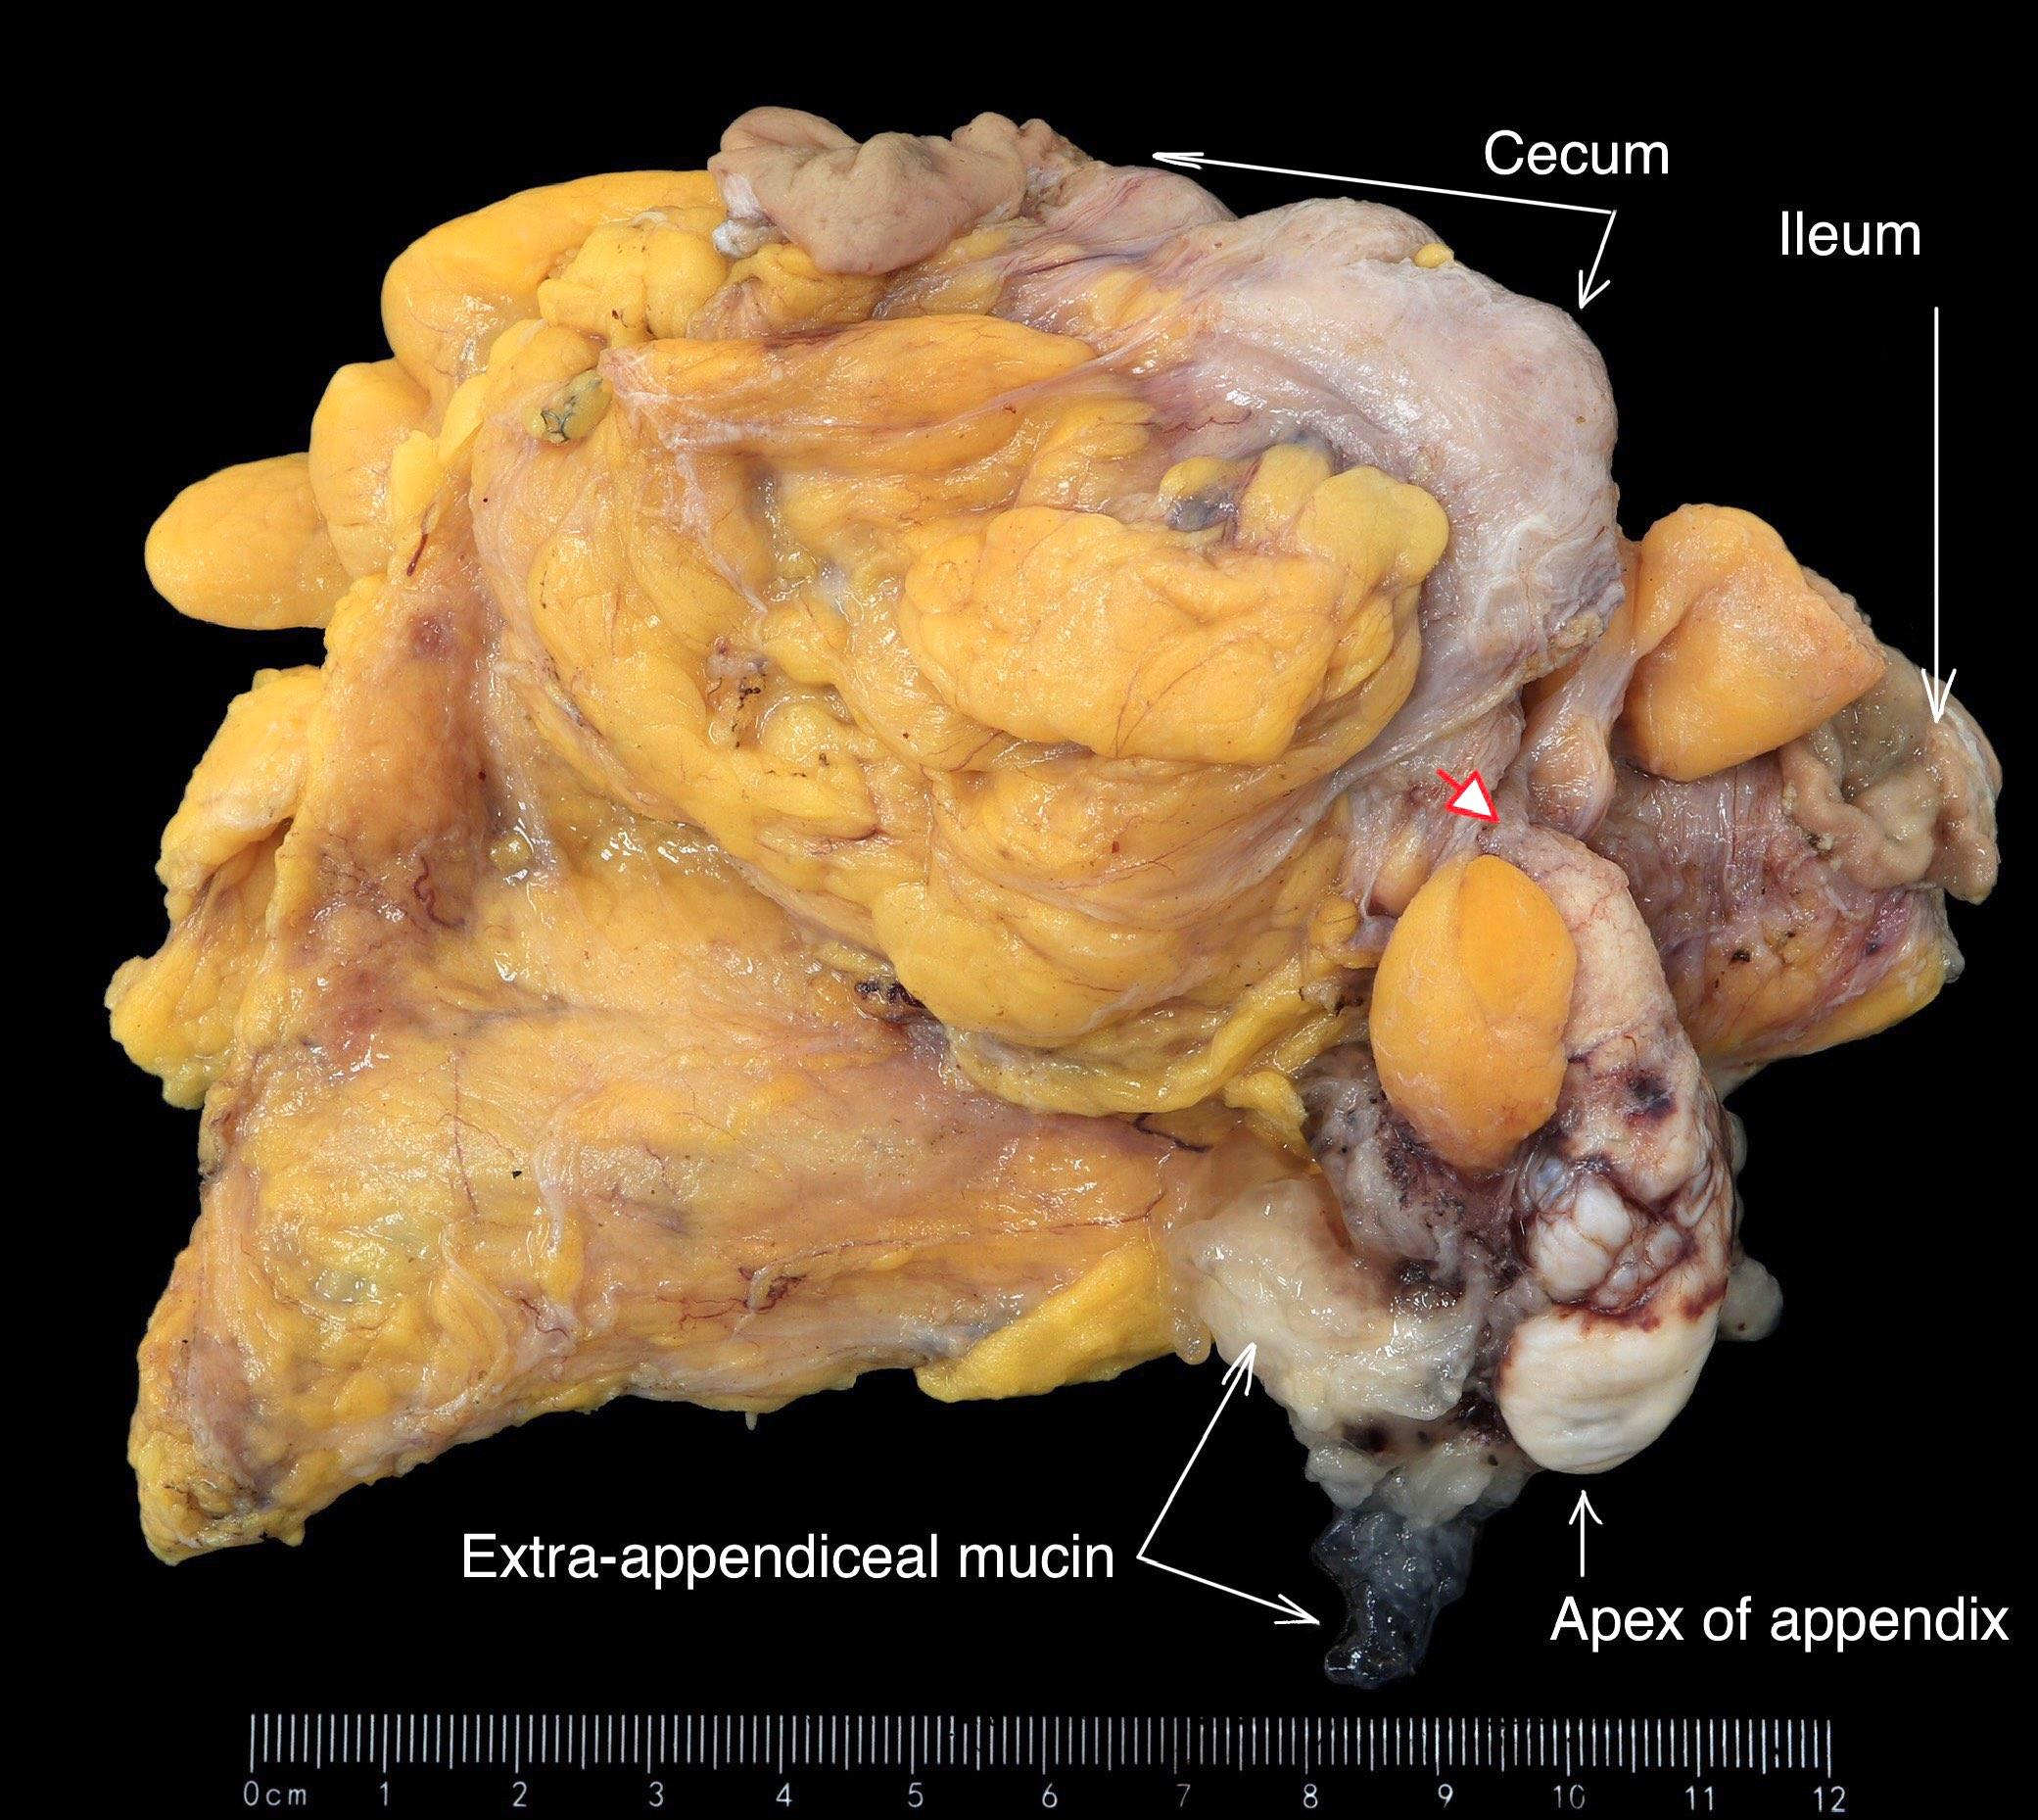

Gross description

- Typically, appendix appears dilated with luminal mucin, although diameter may appear unremarkable

- Serosa appears smooth when appendiceal wall is intact

- Adhesions or extra-appendiceal mucin are concerning for underlying rupture

Gross images

Contributed by Raul S. Gonzalez, M.D. and Michael Feely, D.O.